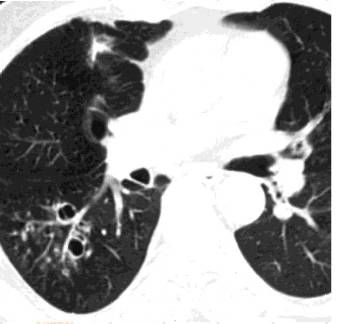

以双肺中、下叶多见,一般由直径2~4mm小叶中心结节影及分支状线影两部分组成,结节较大时刻可达6~8mm。结节边缘清晰,较大时可模糊。分支状线影常呈树枝状,粗细不均匀,边缘可光整或不光整。两者相连,状如树芽。TIB常和肺内其他影像表现同时存在,如支气管扩张时,常和“印戒征”、“轨道征”同时存在;肺结核时可与纤维索条影、片状浸润影、结核空洞及钙化影共存。

树芽征位于肺的周围,正常情况下在肺的周围距胸膜下1cm以内,见不到支气管影像,又因缺乏逐渐变细的特征,而易与正常的小叶中心动脉鉴别。

结核,高分辨率CT显示右肺周围边界不清,大小不等,这些征象代表了支气管内结核的播散